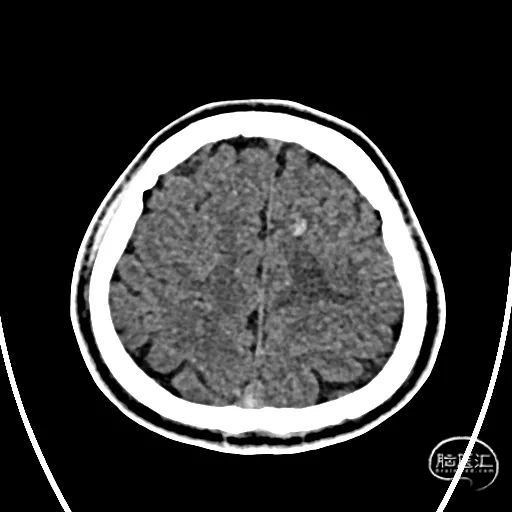

术前CTA/CTP检查,动脉成像未见明显异常,平扫CT可见右侧横窦区域高密度、左侧顶叶片状高密度,窦汇区域、上矢状窦区域高密度充盈。随后紧急性头颅MRV检查,MRV提示上矢状窦及右侧横窦区域不显影。

图注1:1A/1B 平扫CT可见右侧横窦、窦汇区域高密度,额顶叶片状高密度灶

1C 通路CTA检查动脉像未见特殊

1D/1E MRV冠状位及侧位可见上矢状窦及右侧横窦消失,左侧横窦乙状窦部分显影